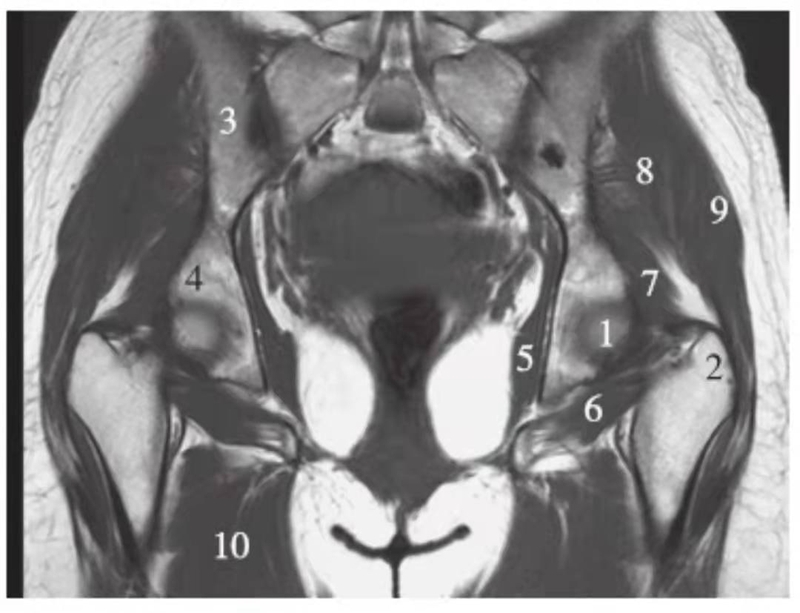

矢状位

正常髋关节经股骨头内缘层面T1WI像

1.髂骨;2.臀大肌;3.圆韧带;4.股骨头;5.坐骨;6.闭孔外肌;7.耻骨肌;8.大收肌

正常髋关节经股骨头中心层面T1WI像

1.臀中肌;2.髂骨;3.臀大肌;4.髂腰肌;5.股骨头骺线;6.股骨头;7.髋臼后唇;8.梨状肌;9.关节囊及髂股韧带;10.闭孔内肌;11.股方肌;12.大收肌

正常髋关节经股骨头外缘层面T1WI像

1.臀中肌;2.臀大肌;3.臀小肌;4.关节囊及髂股韧带;5.髂腰肌;6.股骨颈;7.骨岛;8.股直肌;9.股中间肌